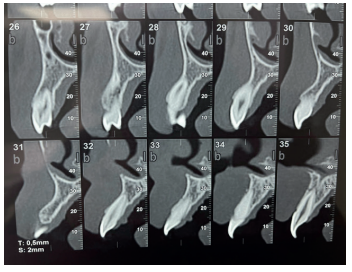

La fluorosis dental es una condición irreversible originada durante el desarrollo dental que genera pigmentaciones intrínsecas, alteraciones en el esmalte manifestadas a manera de manchas blancas, amarillas o marrones, que perjudican la estética y repercuten en el desenvolvimiento social. El presente reporte de caso clínico describe la combinación de los procedimientos de microabrasión y blanqueamiento dental, como alternativas en la eliminación de pigmentaciones dentales. Después del diagnóstico de la patología, verificación de ausencia de lesiones pulpares y caries, una explicación minuciosa a la paciente y obtención del consentimiento informado, se realizó limpieza de las superficies dentales y, bajo aislamiento absoluto, se procedió a realizar la técnica de microabrasión mediante ácido clorhídrico al 6,6% siguiendo las instrucciones del fabricante. Concluido el procedimiento y, observando que era posible mejorar aún más la estética, se decidió ejecutar el procedimiento de blanqueamiento dental, a base de peróxido de hidrógeno al 40% en el consultorio, seguido por peróxido de carbamida al 10% aplicado en el domicilio. Al finalizar el tratamiento se observó uniformidad en el color dental, conjugados con una evidente mejora en la calidad de vida y relación social de la paciente.